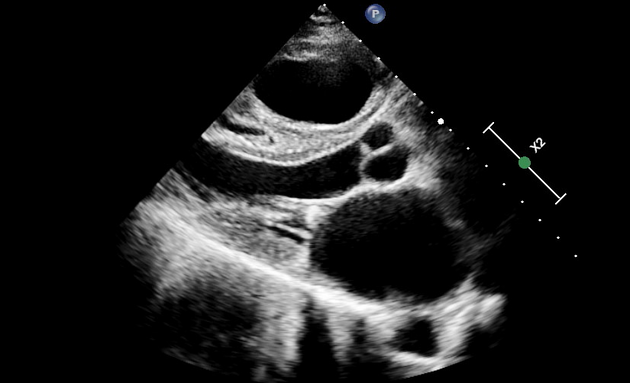

Salut les amis 🎉 Quel est cette examen et quelle est la coupe ? Plus difficile on est ici en diastole, que voyez-vous ? 🌐 La réponse : https://t.co/eygkFKksyG #Radiologie #EDN